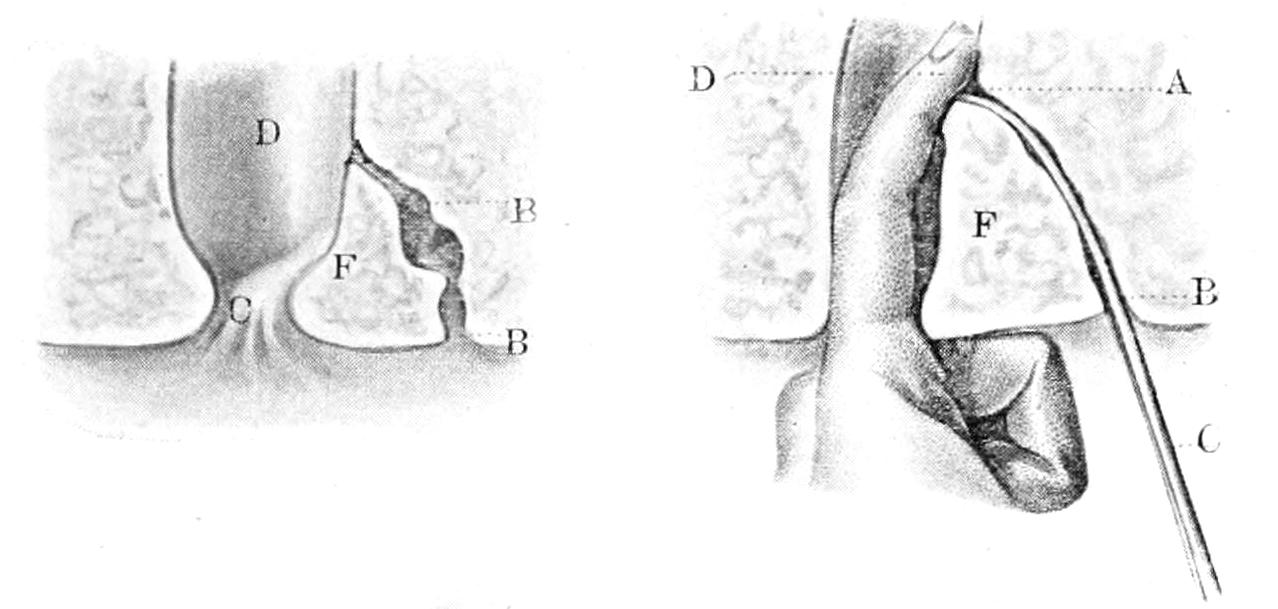

PLATE I

Fig. I.

Fig. II.

Fig. III.

Fig. IV.

Fig. V.

Fig. VI.

Fig. VII.

Fig. VIII.

DRAWN BY J. N. Z. CHASE

PLATE I.

BLOOD.

(Ehrlich triple stain.)

(Prepared by Dr. I. P. Lyon.)

Fig. I. TYPES OF LEUCOCYTES.

a. Polymorphonuclear Neutrophile. b. Polymorphonuclear Eosinophile. c. Myelocyte (Neutrophilic). d. Eosinophilic Myelocyte. e. Large Lymphocyte (large Mononuclear). f. Small Lymphocyte (small Mononuclear).

Fig. II. NORMAL BLOOD.

Field contains one neutrophile. Reds are normal.

Fig. III. ANÆMIA, POST-OPERATIVE (secondary).

The reds are fewer than normal, and are deficient in hæmoglobin and somewhat irregular in form. One normoblast is seen in the field, and two neutrophiles and one small lymphocyte, showing a marked post-hæmorrhagic anæmia, with leucocytosis.

Fig. IV. LEUCOCYTOSIS, INFLAMMATORY.

The reds are normal. A marked leucocytosis is shown, with five neutrophiles and one small lymphocyte. This illustration may also serve the purpose of showing the leucocytosis of malignant tumor.

Fig. V. TRICHINOSIS.

A marked leucocytosis is shown, consisting of an eosinophilia.

Fig. VI. LYMPHATIC LEUKÆMIA.

Slight anæmia. A large relative and absolute increase of the lymphocytes (chiefly the small lymphocytes) is shown.

Fig. VII. SPLENO-MYELOGENOUS LEUKÆMIA.

The reds show a secondary anæmia. Two normoblasts are shown. The leucocytosis is massive. Twenty leucocytes are shown, consisting of nine neutrophiles, seven myelocytes, two small lymphocytes, one eosinophile (polymorphonuclear) and one eosinophilic myelocyte. Note the polymorphous condition of the leucocytes, i. e., their variations from the typical in size and form.

Fig. VIII. VARIETIES OF RED CORPUSCLES.

a. Normal Red Corpuscle (normocyte). b, c. Anæmic Red Corpuscles. d-g. Poikilocytes. h. Microcyte. i. Megalocyte. j-n. Nucleated Red Corpuscles. j, k. Normoblasts. l. Microblast. m, n. Megaloblasts.

The value of a careful blood examination is well illustrated by Plate I, prepared by Dr. Irving P. Lyon, in which are displayed the alterations of greatest interest to the surgeon.